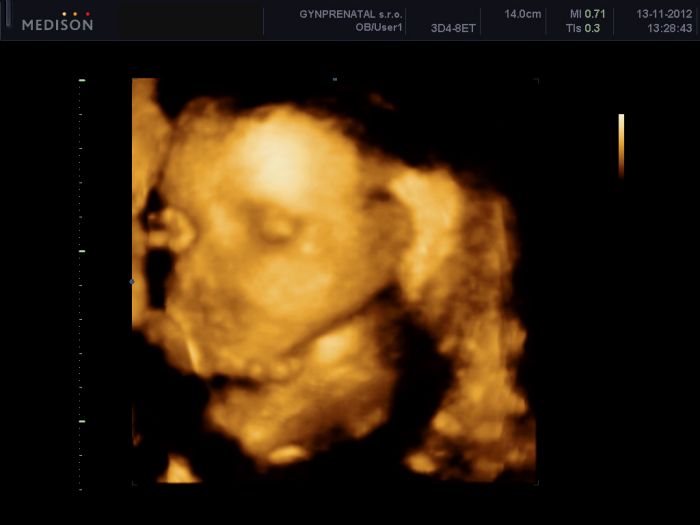

tak se konecne dnes taky hlasím. Byli jsme na tom 3D/4D ultrazvuku. Nachvilinku jsme videli obličejícek noa mame potvrzeného klučinu, pytlik tam byl jasný. Mohlabych se na tu fotečku dívat pořád.

[230016]Tet jsem si všimla, že je tam videt mezi tema nožičkama i toho potvrzeného klučinu

. Předtím jsem si ani nevšimla, jen jsem vam chtela ukazat ty roztomiloučké nožičky.

Jééé Danuš, krásné fotečky s pinďourkem

[230019] Jé, tak konečně vidím taky někde na UTZ fotce pindika a musim podotknout, ze toho my tam fakt nemame